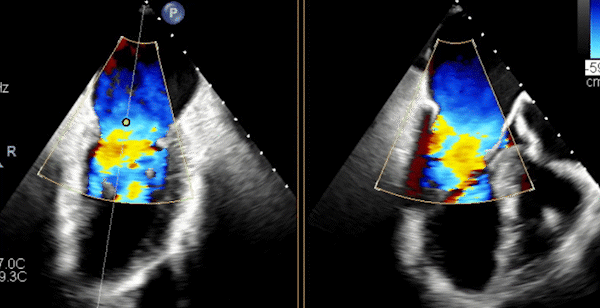

心脏超声示左室增大,二尖瓣2、3区脱垂伴重度反流(腱索断裂),Carpentier分型Ⅱ型,典型Barlow综合征表现;二尖瓣开放面积5.0cm²,3区瓣环内径31mm,前叶长22mm、后叶17mm,前叶收缩期关闭瓣体部分呈拱形突向左房腔,瓣膜游离缘对合欠佳,可见腱索断裂,长度9mm;2区瓣环内径32mm,前叶长22mm、后叶10mm,前后叶均可脱垂;三尖瓣重度反流。CDFI示瓣口重度偏心性反流,反流束沿主动脉后壁走行,肺静脉收缩期可见反向频谱。

术前反流

图片